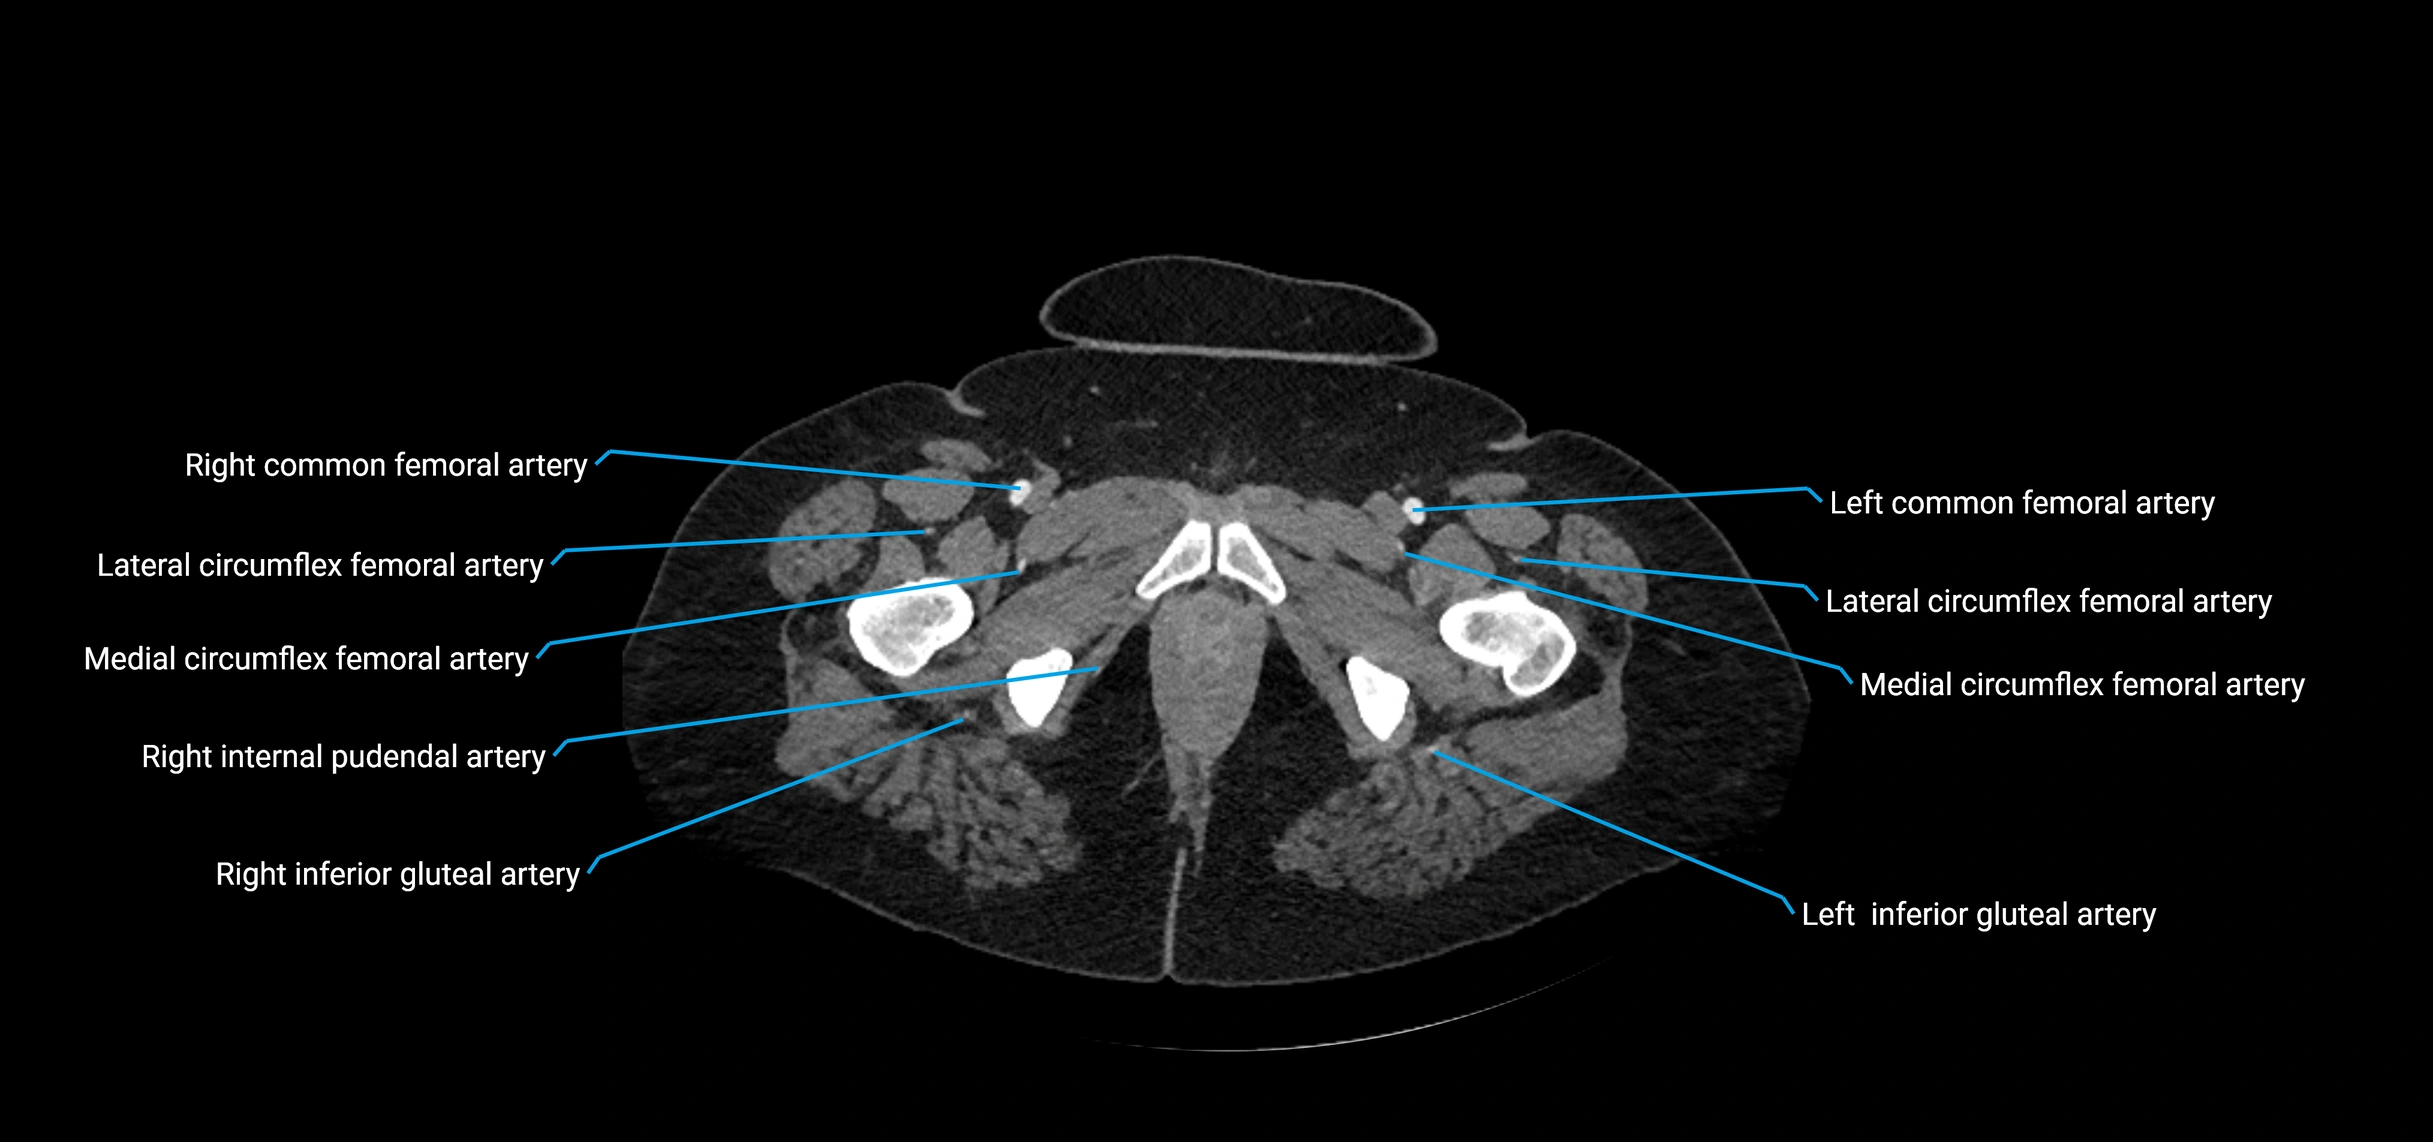

Contrast-enhanced CT (CTA):

• Gold standard for abdominal aortic imaging

• Provides excellent detail of lumen, wall, aneurysm, thrombus, and branch vessels

• Multiplanar and 3D reconstructions help in aneurysm measurement, stent graft planning, and dissection evaluation

• Detects acute rupture, traumatic injury, or occlusion with high sensitivity